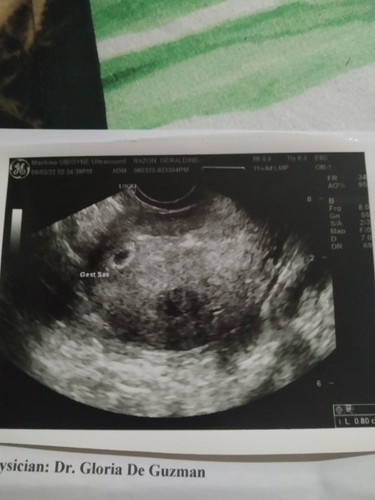

sino ang naka encounter na ng empty sac? Nag develop ba ang embryo sa loob nito?

Empty gestational sac

At 5weeks yolksac seen no embryo pa at walang Heartbeat pinabalik ako after 2weeks ayon nakita na si baby ko.. Sa ngayon eto na siya buhat ko 3months old healthy baby😊 Pray ka lang mi na madevelop si baby..ilan weeks ka na ba? At sundin mo kung may ipainom sayo gamot si OB

Magbasa pa6th week na ngayon. Next week babalik ako for TVS and check up after. Taking vitamins din, folic acid and 2 pampakapit. I had a miscarriage na kasi nun Apr 2020, no cardiac activity ang nangyari kaya abot abot talaga ang dasal ko 🙏🙏🙏